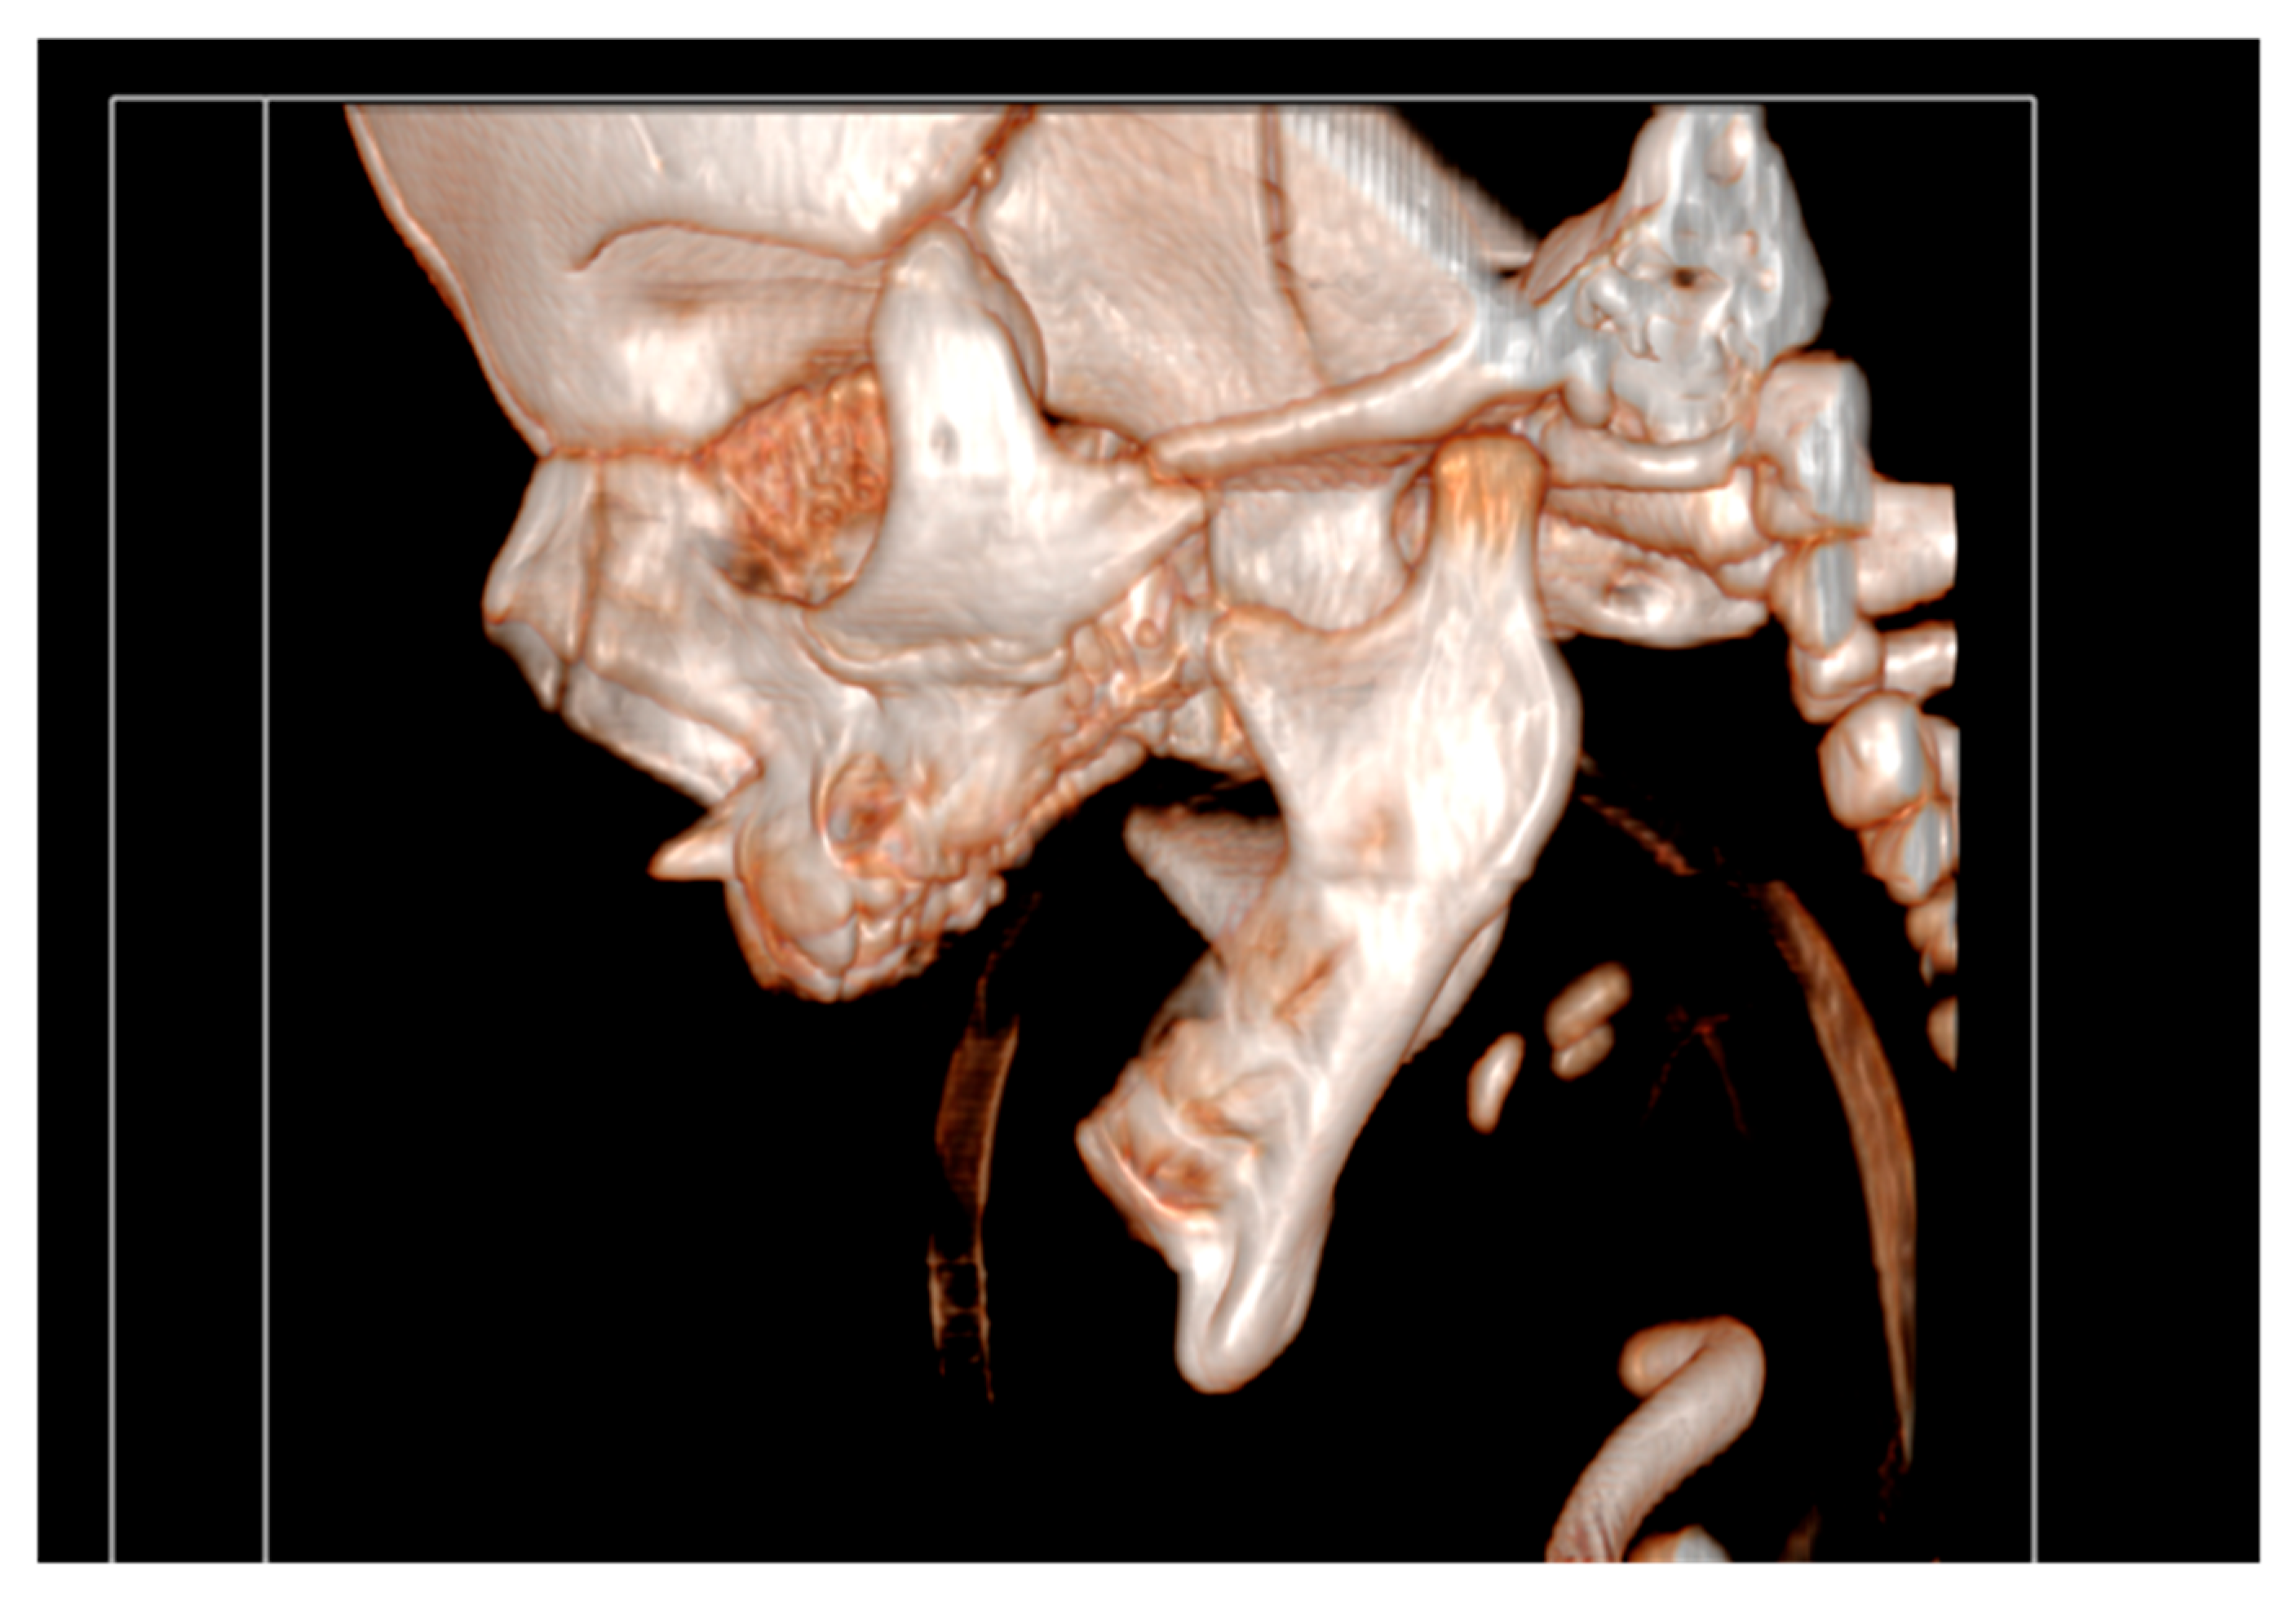

It had underdeveloped body region and pointed chin. Only three tooth germs of the lower frontal teeth were present, specifically one lower medial incisor and two lateral incisors. Temporomandibular joints were normal (Figure 4).

Figure 4. Temporomandibular joints are normal.